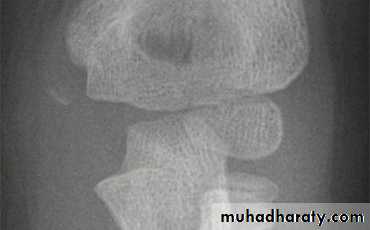

X-ray : the fracture is seen clearly in A-P , and lateral views . In undisplaced fracture the

fat-pad sign which is triangular lucency in front of the distal humerus this will raise the

suspicion of the fracture.

In A-P view we can measure the Boumans’ angle which is helpful in assessing the degree of angulation of the distal segment normally less than 80`.

Boumann`s angle